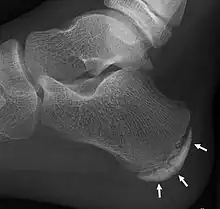

| X-ray of the foot of an 11-year-old child, showing sclerosis and fragmentation of the calcaneal apophysis. This is a sign of low sensitivity and specificity of Sever's disease, because those with Sever's disease may not have it, and this appearance is also present in feet without pain.[1] | |

Children with calcaneal apophysitis commonly complain of pain at the back of the heel. This pain increases with jumping and some running sports. Sometimes, the pain makes children limp and may result in poor sports performance or them not wanting to participate in some sports. The back of the heel is never swollen or red, unless there has been shoe rubbing. When the back of the heel is squeezed from the inside and outside, children with calcaneal apophysitis will report pain. Foot radiographs are not needed to diagnose calcaneal apophysitis as the growth plate can look similar with or without pain. Health professionals should only refer for imaging when the symptoms don't match with the usual presentation or there has been an injury that has resulted in heel pain. Therefore, the diagnosis of Sever's disease is primarily from history and physical assessment.[2]